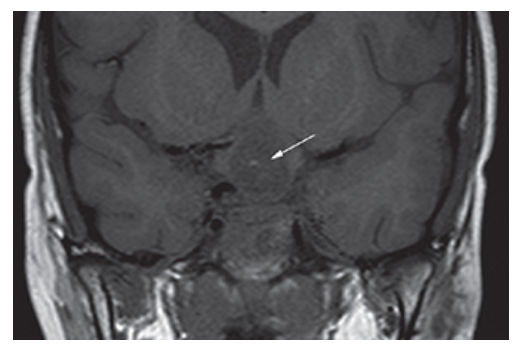

Craniopharyngioma. Coronal T1W MR image shows a low-signal suprasellar mass (arrow) with small focus of increased signal which enhances with contrast.

Craniopharyngioma. Postcontrast T1W coronal MR.